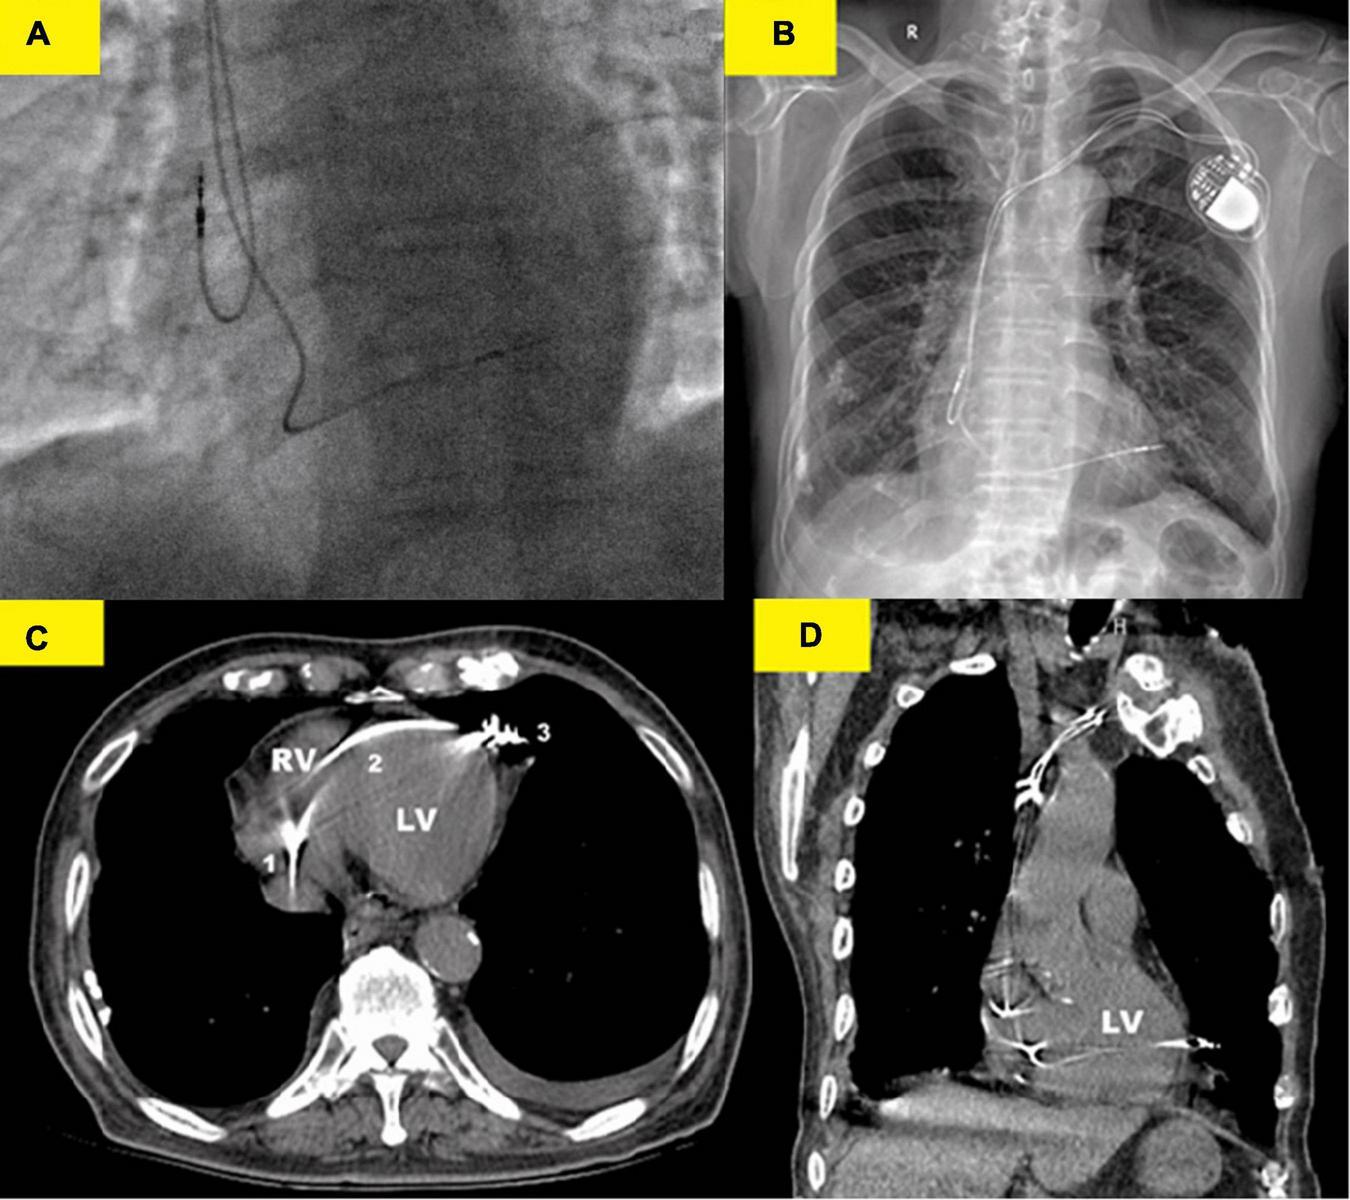

FIGURE 2

Various imaging modalities showed the lead perforation. (A) X-ray fluoroscopy image (right anterior oblique 30°) immediately after implantation showed that the RV lead was placed at the right ventricular (RV) apex. (B) Chest x-ray showed that the RV lead was beyond the left cardiac margin and clearly migrated in the left hemithorax. (C) Thoracic computed tomography (CT) scan showed the RV lead course from the right ventricle (1) to the left cardiac margin (3) in the patient and perforation of the interventricular septum (2) was well-evident. (D) Coronal CT images confirmed the RV lead migration in the left hemithorax. Thoracic CT scan should, therefore, be regarded as the gold standard for the strategical management of this complication.

We performed dual-chamber PM (HeartTone LD300D, LifeTech Scientific Corporation, Shenzhen, China) implanted via the left subclavian vein on the next day after admission. The implantation procedure can be summarized as follows: under local anesthesia, after a successful puncture of the left subclavian vein, the patient was implanted with a common sheath. Although a superior vena cava stenosis might exist, we did not replace the common sheath with a long sheath. Thus, the manipulation of active fixation leads was very difficult; we attempted to fix RV lead at the RV septum, but it was not as successful. Finally, two active fixation leads were, respectively, placed at the RV apex (SureScan 5076; 58 cm, Medtronic, Minneapolis, MN, USA) and the right atrial appendage (SureScan 5076; 52 cm, Medtronic, Minneapolis, MN, USA) with excellent pacing parameters (intraoperative RV lead impedance and threshold were 1,300 Ω and 1.4 V, respectively). There were no abnormalities or complications during the implantation procedure. X-ray fluoroscopy image immediately after implantation showed that the RV lead was fixed properly (Figure 2A). Electrocardiogram immediately after implantation showed the left bundle branch block pattern (Figure 1B).

However, on the second postoperative day (POD), the patient complained of unrelenting chest pain and syncope. A subsequent immediate chest X-ray identified that the RV lead tip migrated to the region outside the left cardiac margin (Figure 2B). A thoracic computed tomography (CT) scan revealed that the RV lead passed through the interventricular septum and the left LV free wall, and finally reached the left of the pericardial cavity. Furthermore, as the thoracic CT scan also showed a small amount of left pleural effusion (Figure 2B) and there were no obvious symptoms of pericardial tamponade (Figures 2C, D), we deduced that the lead had already penetrated the pericardium. Electrocardiogram and interrogation showed loss of ventricular capture (Figure 1C).